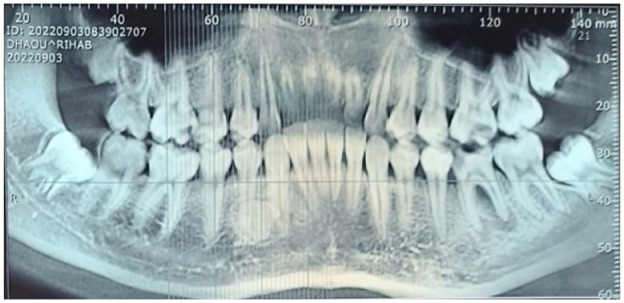

Calcifying odontogenic cyst, also known as Gorlin cyst is a rare benign cystic lesion primarily found in the jawbones, accounting less than 1% of odontogenic cysts. It can be associated with odontogenic tumors such as odontomas. We report a rare case of COC associated with complex odontoma in a young patient and discuss its clinical features, diagnosis, and treatment options. An 18-year-old female patient presented with a painless radiopaque lesion of the right mandibular bone at Oral Medicine and Oral Surgery department. Radiographs revealed irregular tooth-like structures in the canine-premolar area. The lesion was surgically removed, and histopathology confirmed COC with a complex odontoma. As of the World Health Organization's 2022 definition, COC is a developmental odontogenic cyst characterized by calcified ghost cells. It typically affects individuals during their second and third decades of life, with no gender preference, almost equally in the maxilla and the mandible. The main treatment is total enucleation, with a generally favorable prognosis. Histopathology is essential for diagnosis due to its mimicry of other jaw conditions. Long-term follow-up is needed to prevent recurrences.

Abstract Image